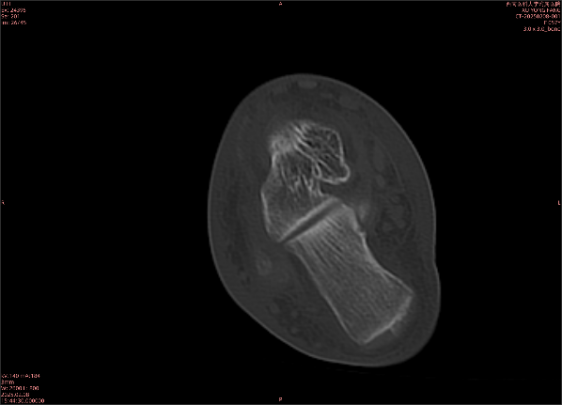

隱性骨折在MRI表現(xiàn)為T1WI序列上見由關(guān)節(jié)面向骨干走行的形態(tài)各異低信號區(qū),有線狀、條狀、紊亂低信號,信號強(qiáng)度不均勻。與T1WI低信號改變相對應(yīng)部位在T2WI上表現(xiàn)為相應(yīng)形狀的高、低混雜信號,且部分低信號周圍可見高信號水腫改變。STIR序列圖像上病灶呈顯著高信號,與信號被抑制的臨近正常骨髓形成鮮明對比,分界也較T2WI成像更為清楚。脂肪組織抑制技術(shù)是MRI的一個(gè)重要性能,脂肪抑制技術(shù)在MRI應(yīng)用中可以改善組織對比和增加病變顯示機(jī)會,這樣骨髓的脂肪抑制后就不會有任何信號,而隱性骨折線及骨髓水腫的異常高信號就會更加明顯的顯示出來。

由于無骨皮質(zhì)中斷,尚不足以引起X線衰減系數(shù)的明顯改變,X線平片無異常征象;CT在顯示骨皮質(zhì)及軟組織異常方面明顯優(yōu)于傳統(tǒng)X線,特別是三維重建能夠有效的評價(jià)復(fù)雜骨折,骨外傷CT檢查應(yīng)用廣泛,但CT對隱性骨折的顯示亦極為有限。

專業(yè)解釋看不懂沒關(guān)系,大家看圖1和圖2就可以了,這是同一個(gè)患者跟骨的磁共振和CT圖像,圖1的紅色箭頭指示的黑線就是磁共振圖像顯示的骨折線,一目了然。而對比圖2的CT圖像上并未顯示異常。

這下大家明白了吧,如果懷疑隱匿性骨折優(yōu)先選擇磁共振檢查